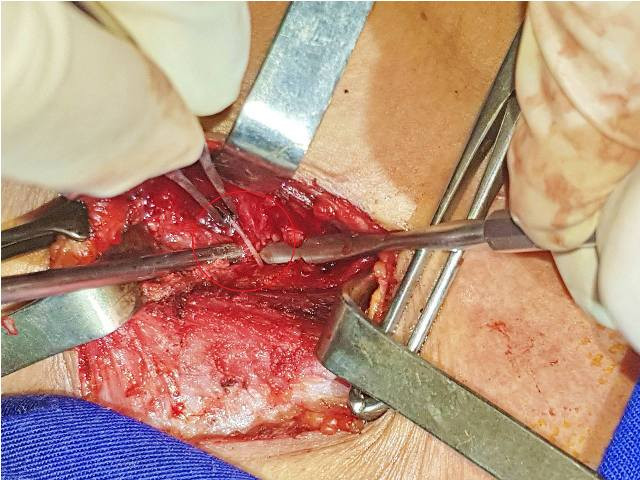

Đến chiều 30/11, bệnh nhân được tiến hành phẫu thuật mở cạnh cổ và mở tuyến giáp. Do tổn thương phức tạp, các bác sĩ đã phải mất 1 giờ đồng hồ để tìm kiếm dị vật và phát hiện ra dị vật là chiếc xương cá sắc nhọn dài 2,5cm nằm trong tuyến giáp và chạy dọc theo bờ ngoài của tuyến giáp, chạy song song với trục cơ thể (song song với khí quản nên việc tìm kiếm rất khó khăn).

Hình ảnh chiếc xương cá sắc nhọn dài 2,5cm được lấy ra.

“Đây là trường hợp khá hi hữu, xương cá sắc nhọn đâm qua thực quản rồi chạy vào vùng cổ đâm xuyên và nằm trong tuyến giáp. Đặc biệt nguy hiểm nếu dị vật chạy vào vùng nền cổ, phải lọc, bóc tách bó mạch cảnh mới tìm được dị vật nằm trong ổ viêm”- ThS. Thắng nói.